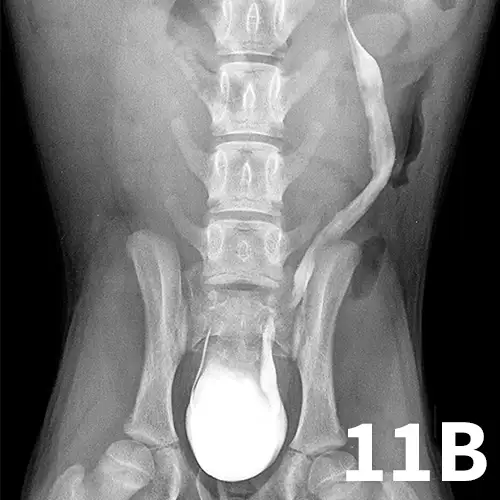

Normal ureters cannot be visualized with survey radiography or ultrasonography, but normal and abnormal ureters are readily visualized with excretory urography. The location of a ureteral obstruction or rupture as well as the presence of an ectopic ureter (especially when combined with pneumocystography) can be documented with excretory urography (Figure 11). A dilated ureter (hydroureter) can be observed with ultrasonography (Figure 12). Pyelocentesis (for cytology and culture) and antegrade pyelography (nephropyelography) (Figure 13) to document obstruction or leakage can be conducted via ultrasound guidance with heavy sedation or anesthesia. Ultrasonography can also be used to visualize retroperitoneal fluid accumulation, which may occur with a ureteral rupture, hemorrhage, or infectious or neoplastic disease. Whereas ureteroliths without hydroureter may be missed on ultrasonography, radiopaque ureteroliths can be observed on survey radiography (Figure 14). Survey radiographic visualization of radiopaque ureteroliths may be facilitated by enemas to empty the colon of fecal material and/or use of a radiolucent paddle to apply regional compression over the ureter to separate adjacent organs (eg, loops of bowel) (Figure 15). Aged cats with chronic kidney disease (CKD) frequently have calcium oxalate nephroliths; in some cases, these nephroliths will migrate into the ureters. Survey radiographs should be employed to rule out ureterolithiasis, especially in cats with acute decompensation of their CKD (Figure 16).

Figure 11A.

Lateral oblique view from a young dog with a left ectopic ureter that was diagnosed with excretory urography. The left ureter and renal pelvis are dilated. The left ureter extends beyond the trigone region of the urinary bladder on the lateral oblique view (arrow).